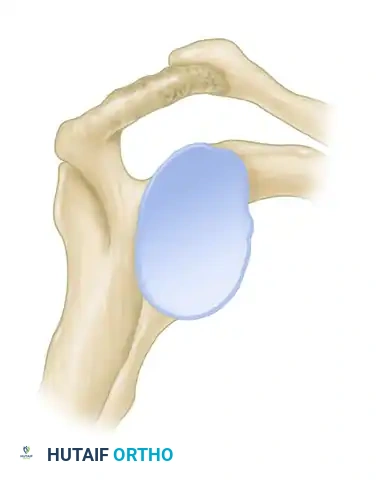

Figure 46-4 (Type II): A curved acromion that parallels the contour of the humeral head, moderately reducing the subacromial space.